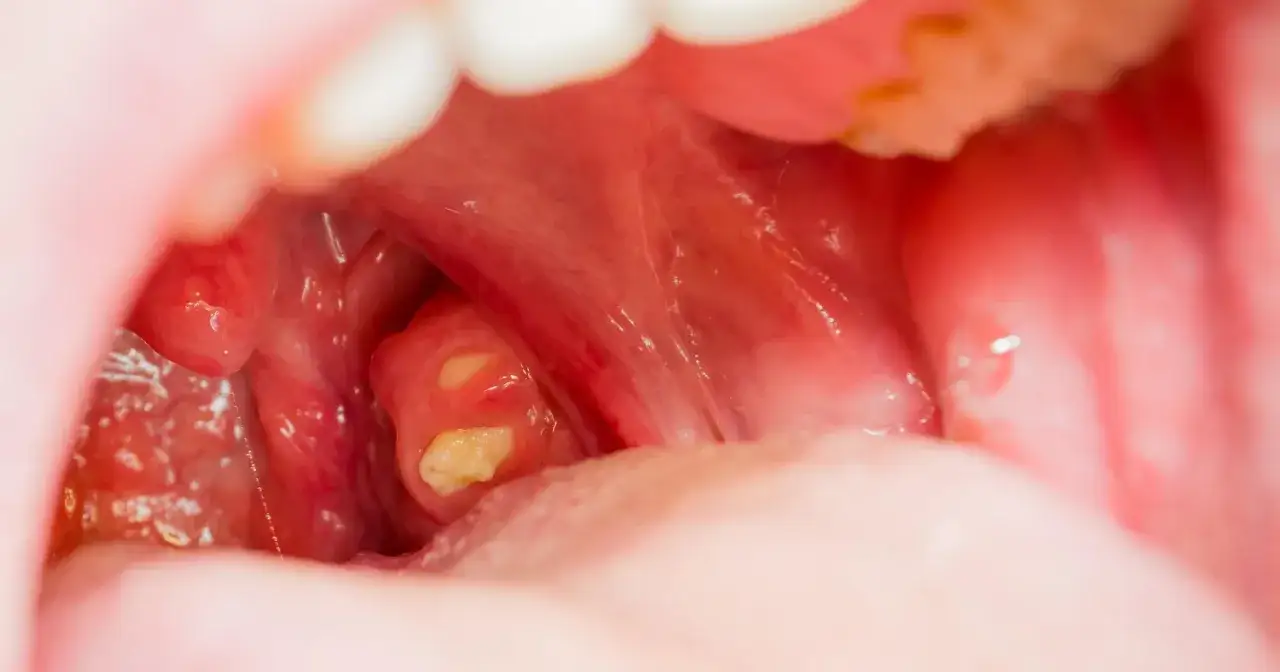

Kiedy zauważamy w gardle coś, co wygląda jak białe lub żółtawe grudki, naturalnie pojawia się niepokój. Te tajemnicze twory to właśnie kamienie migdałkowe, znane w terminologii medycznej jako czopy retencyjne. Są to niewielkie złogi, które tworzą się w naturalnych zagłębieniach, czyli kryptach, migdałków podniebiennych. Ich skład jest dość złożony: to mieszanina resztek jedzenia, martwych komórek nabłonka, komórek odpornościowych oraz bakterii, które z czasem ulegają procesowi zwapnienia. Choć problem ten może dotyczyć nawet 10% populacji, co potwierdzają dane z portali medycznych takich jak Dr. Max, w większości przypadków kamienie migdałkowe nie są uważane za groźne dla zdrowia. To bardzo ważna informacja, która powinna przynieść ulgę wielu osobom.

Aby lepiej zrozumieć kamienie migdałkowe, warto przyjrzeć się ich budowie i procesowi powstawania. Migdałki podniebienne, choć pełnią ważną funkcję w układzie odpornościowym, posiadają liczne krypty – czyli niewielkie, naturalne zagłębienia i szczeliny. To właśnie w tych kryptach gromadzą się różnorodne substancje: mikroskopijne resztki pokarmowe, złuszczone martwe komórki nabłonka z jamy ustnej, a także komórki odpornościowe, które walczyły z infekcjami. Do tego dochodzą bakterie, zwłaszcza te beztlenowe, które doskonale czują się w takim środowisku. Z czasem, pod wpływem soli mineralnych obecnych w ślinie, ta organiczna masa ulega zwapnieniu, tworząc twarde, białe lub żółtawe grudki. Ich rozmiar może wahać się od ziarenek piasku po większe, kilkumilimetrowe twory. To naturalny proces, który nie zawsze jest związany z chorobą, ale często wynika ze specyficznej anatomii migdałków i warunków panujących w jamie ustnej.

- Białe lub żółtawe grudki widoczne na migdałkach – czasem można je dostrzec samodzielnie, patrząc w lustro.